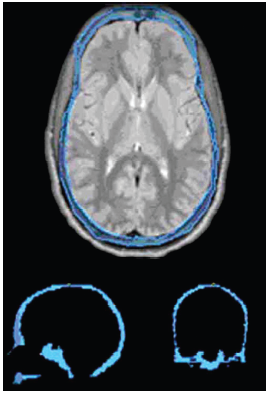

Comparison between Magnetic Resonance Imaging Estimates of Extracranial Cerebrospinal Fluid Volume and Physical Measurements in Healthy Dogs

Publication: Vet Radiol Ultrasound. 2015 Nov;56(6):658-65. PMID: 26311617 Authors: Reinitz LZ, Bajzik G, Garamvölgyi R, Petneházy Ö, Lassó A, Abonyi-Tóth Z, Lőrincz B, Sótonyi P. Institution: Faculty of Veterinary Science, Department of Anatomy and Histology, Szent István University, Godollo, Hungary. Background/Purpose: Dosages for myelography procedures in dogs are based on a hypothetical proportional relationship between bodyweight and cerebrospinal fluid (CSF) volume. Anecdotal radiographic evidence and recent studies have challenged the existence of such a defined relationship in dogs. The objectives of this prospective cross-sectional study were to describe CSF volumes using magnetic resonance imaging (MRI) in a group of clinically healthy dogs, measure the accuracy of MRI CSF volumes, and compare MRI CSF volumes with dog physical measurements. A sampling perfection with application optimized contrast using different flip-angle evolution MRI examination of the central nervous system was carried out on 12 healthy, male mongrel dogs, aged between 3 and 5 years with a bodyweight range of 7.5-35.0 kg. The images were processed with image analysis freeware (3D Slicer) in order to calculate the volume of extracranial CSF. Cylindrical phantoms of known volume were included in scans and used to calculate accuracy of MRI volume estimates. The accuracy of MRI volume estimates was 99.8%. Extracranial compartment CSF volumes ranged from 20.21 to 44.06 ml. Overall volume of the extracranial CSF increased linearly with bodyweight, but the proportional volume (ml/bodyweight kilograms) of the extracranial CSF was inversely proportional to bodyweight. Relative ratios of volumes in the cervical, thoracic, and lumbosacral regions were constant. Findings indicated that the current standard method of using body weight to calculate dosages of myelographic contrast agents in dogs may need to be revised. |